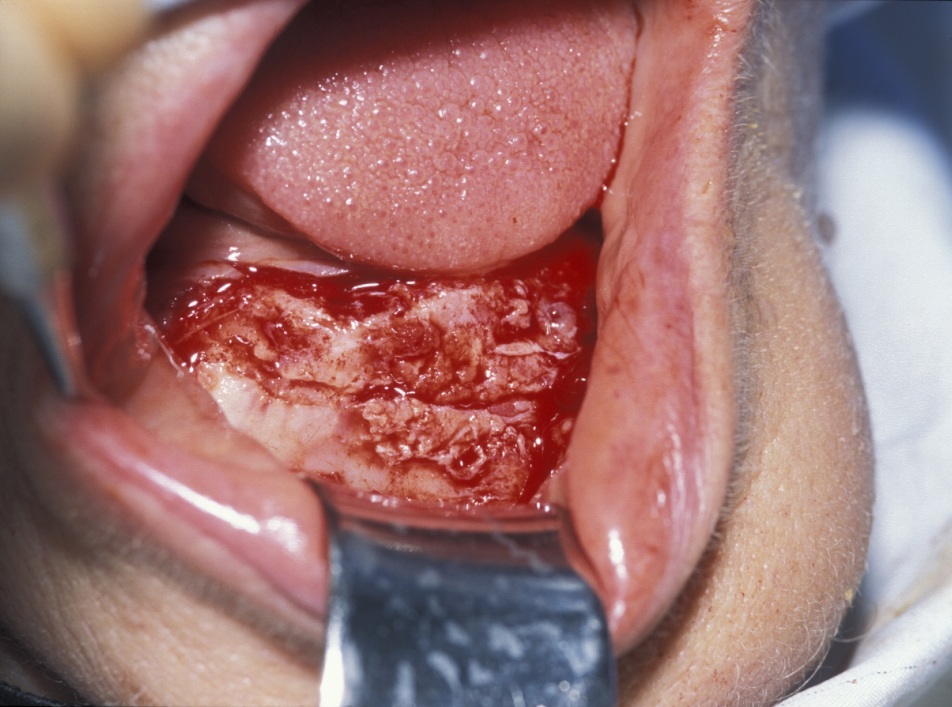

Figure 2: Buccal cortex (outer hard shell of bone) is removed to create a bone window for enucleation of the cyst.

Figure 3: The plane between the cyst lining and the bone cavity is bluntly dissected.

Figure 4: Teasing the cyst by direct traction and dissection delivers the cyst.